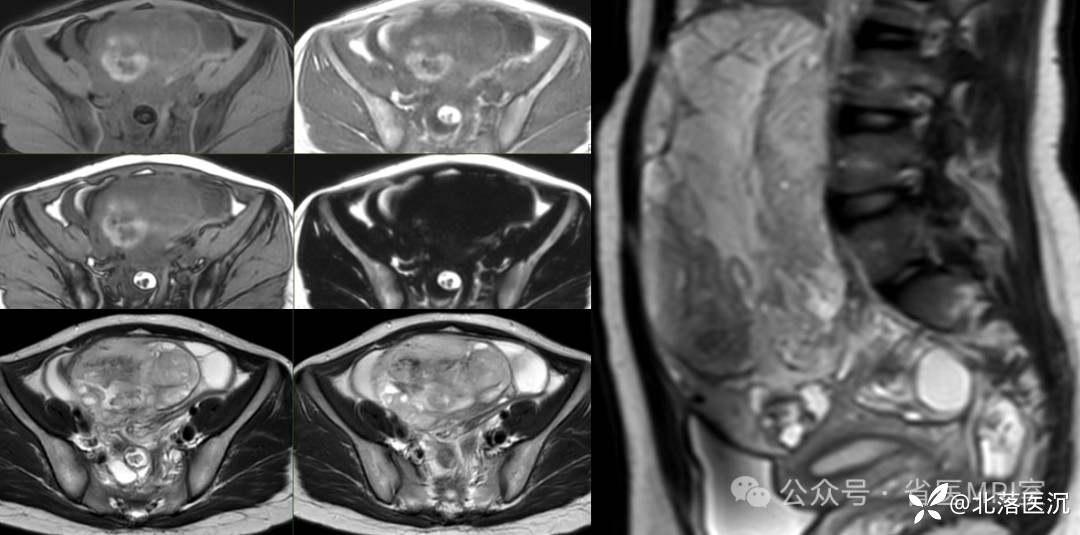

影像学表现:

CT表现:呈囊性,外形一般为圆形或类圆形,其内可见特征性脂肪密度影、头结节、钙化灶、牙齿等

MRI表现:单囊或多囊的含脂肿块,大多包膜完整,病变内脂肪成分表现为T1WI、T2WI高信号影,脂肪抑制序列呈低信号改变;头发、牙齿及骨骼在各序列均为低信号改变;头结节信号表现多样,与头结节内含有多胚层结构有关

增强扫描:实性部分多无明显强化